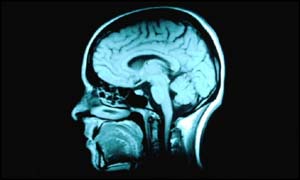

The scientists scanned the brains of patients

Brain scans

They carried out brain scans on 21 men with sleep apnoea and 21 men without the condition.

The scans revealed that men with sleep apnoea had significantly fewer brain cells in areas of the brain that control speech, movement and emotion.